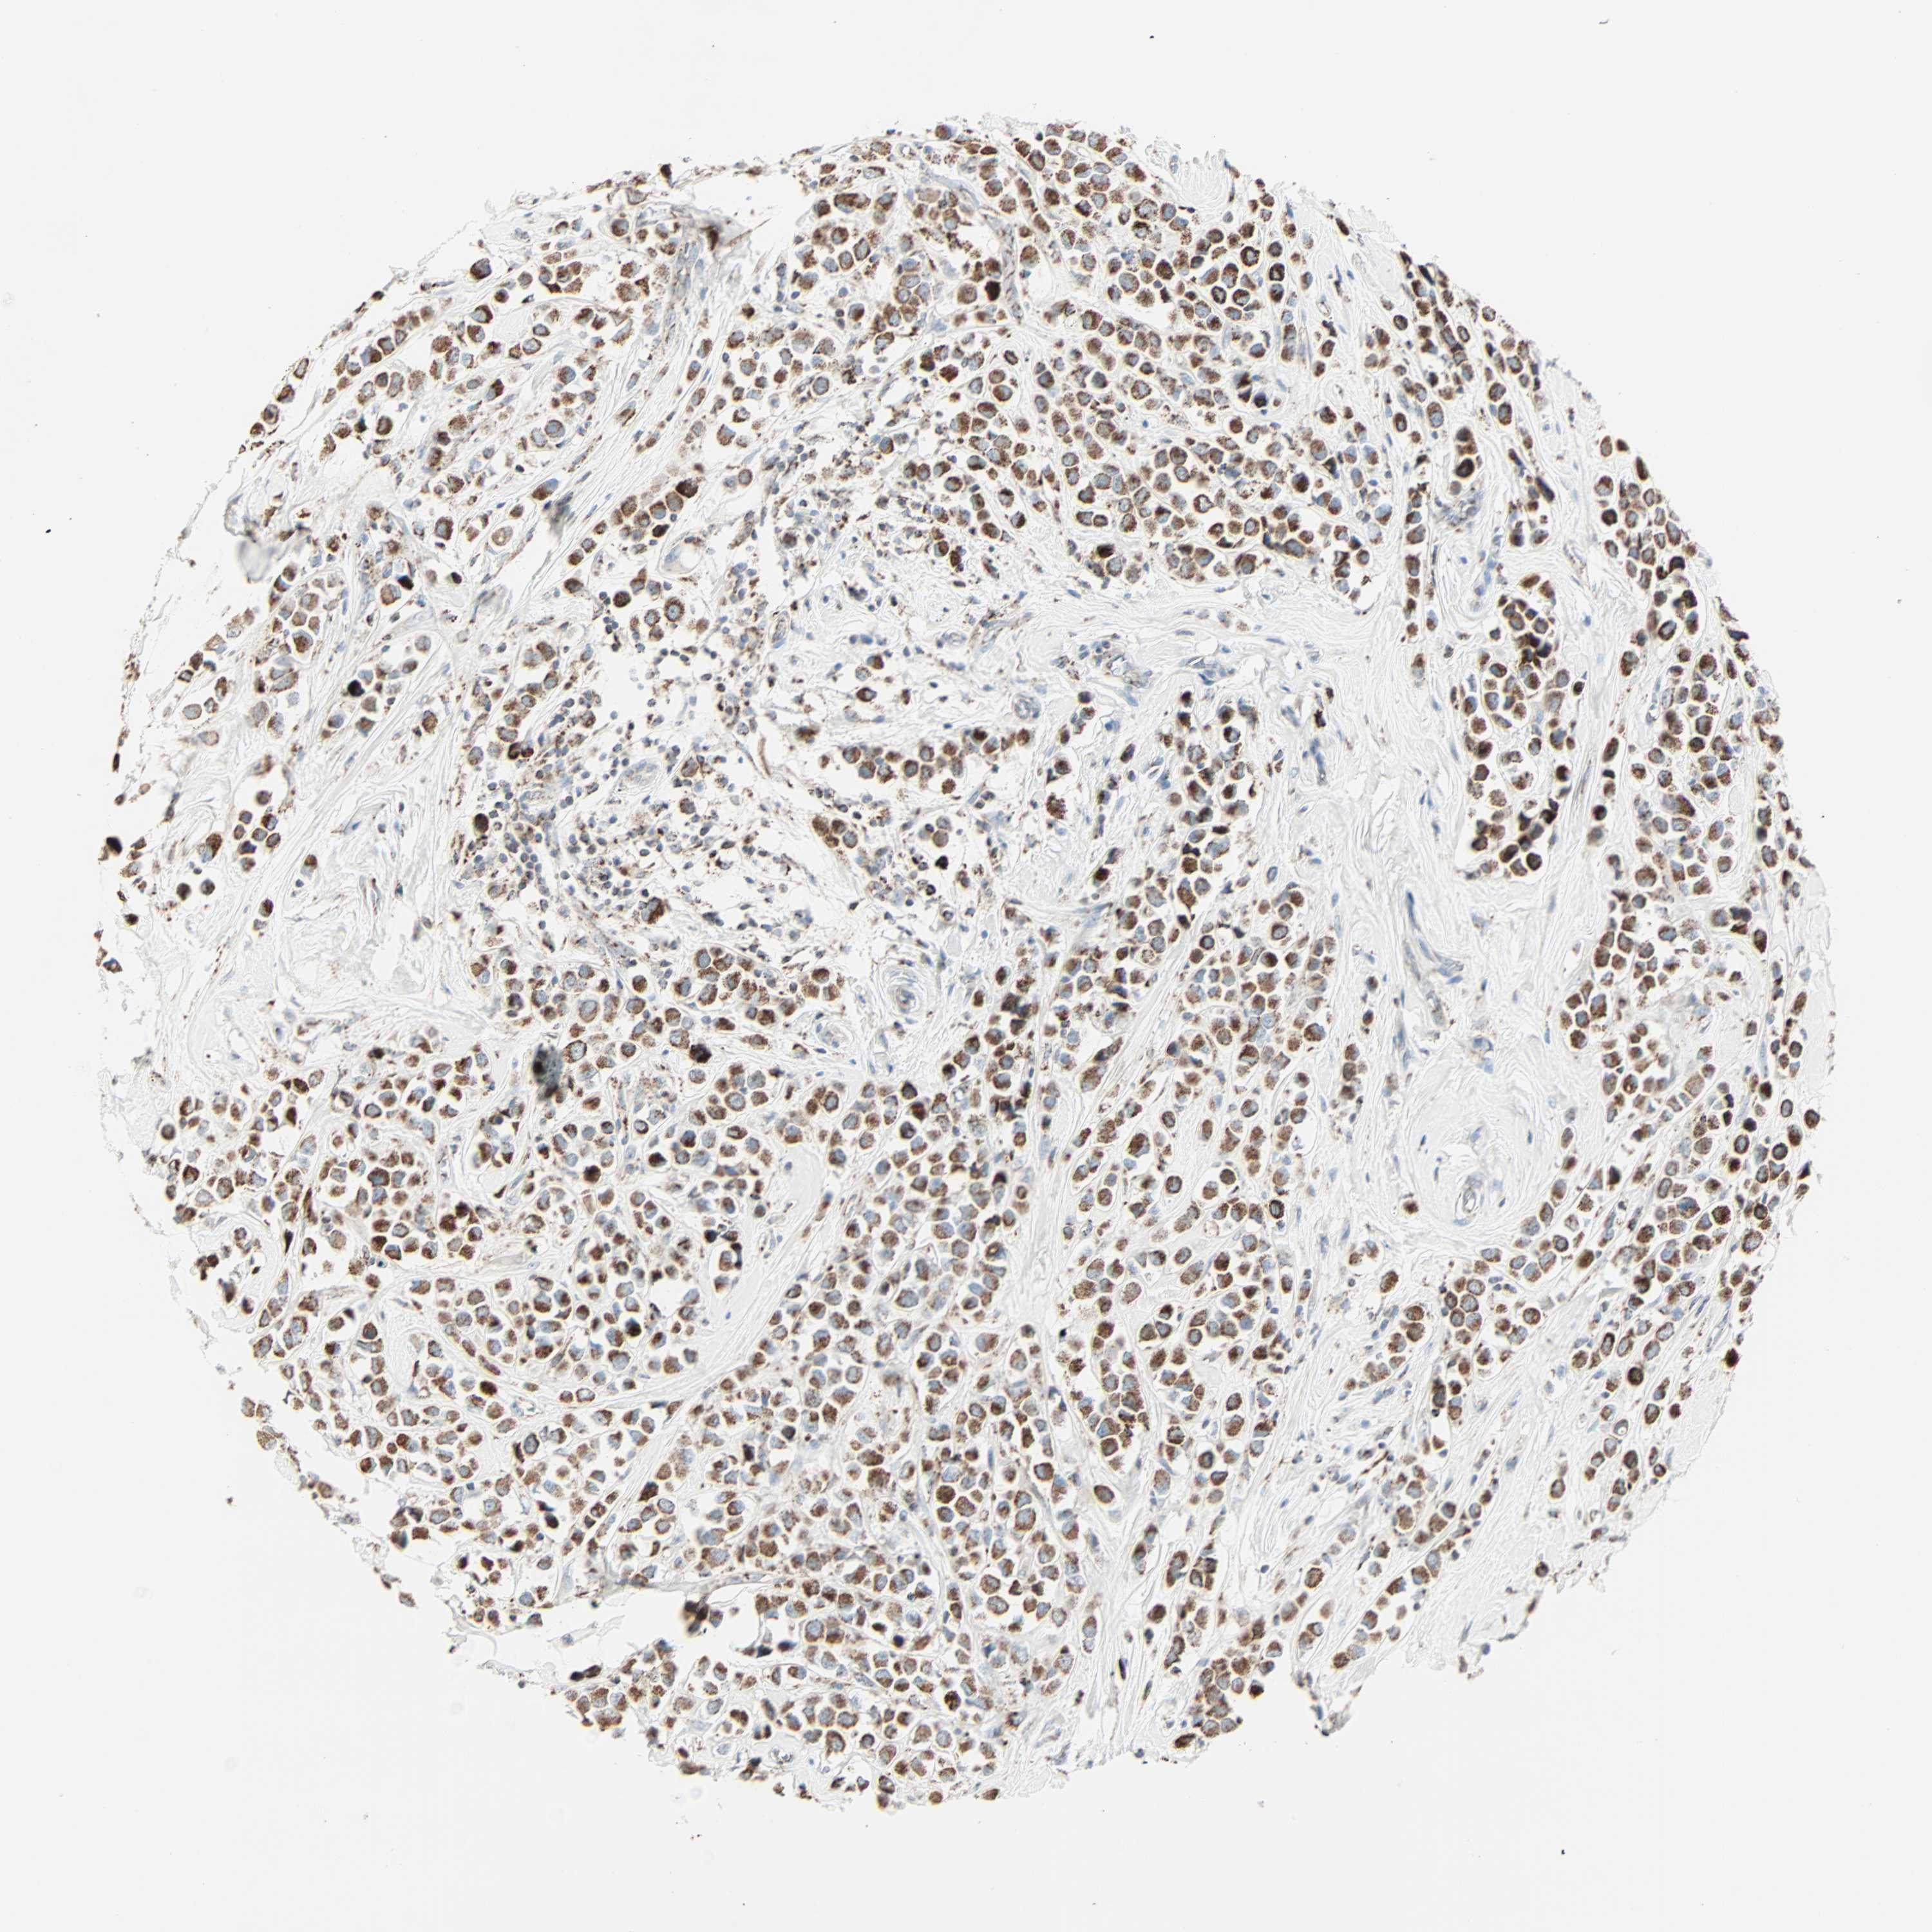

CANCER BREAST CANCER Show tissue menu

BRCA TCGA BRCA VALIDATION PROTEIN EXPRESSION

Breast cancer

Human cancer

Breast invasive carcinoma